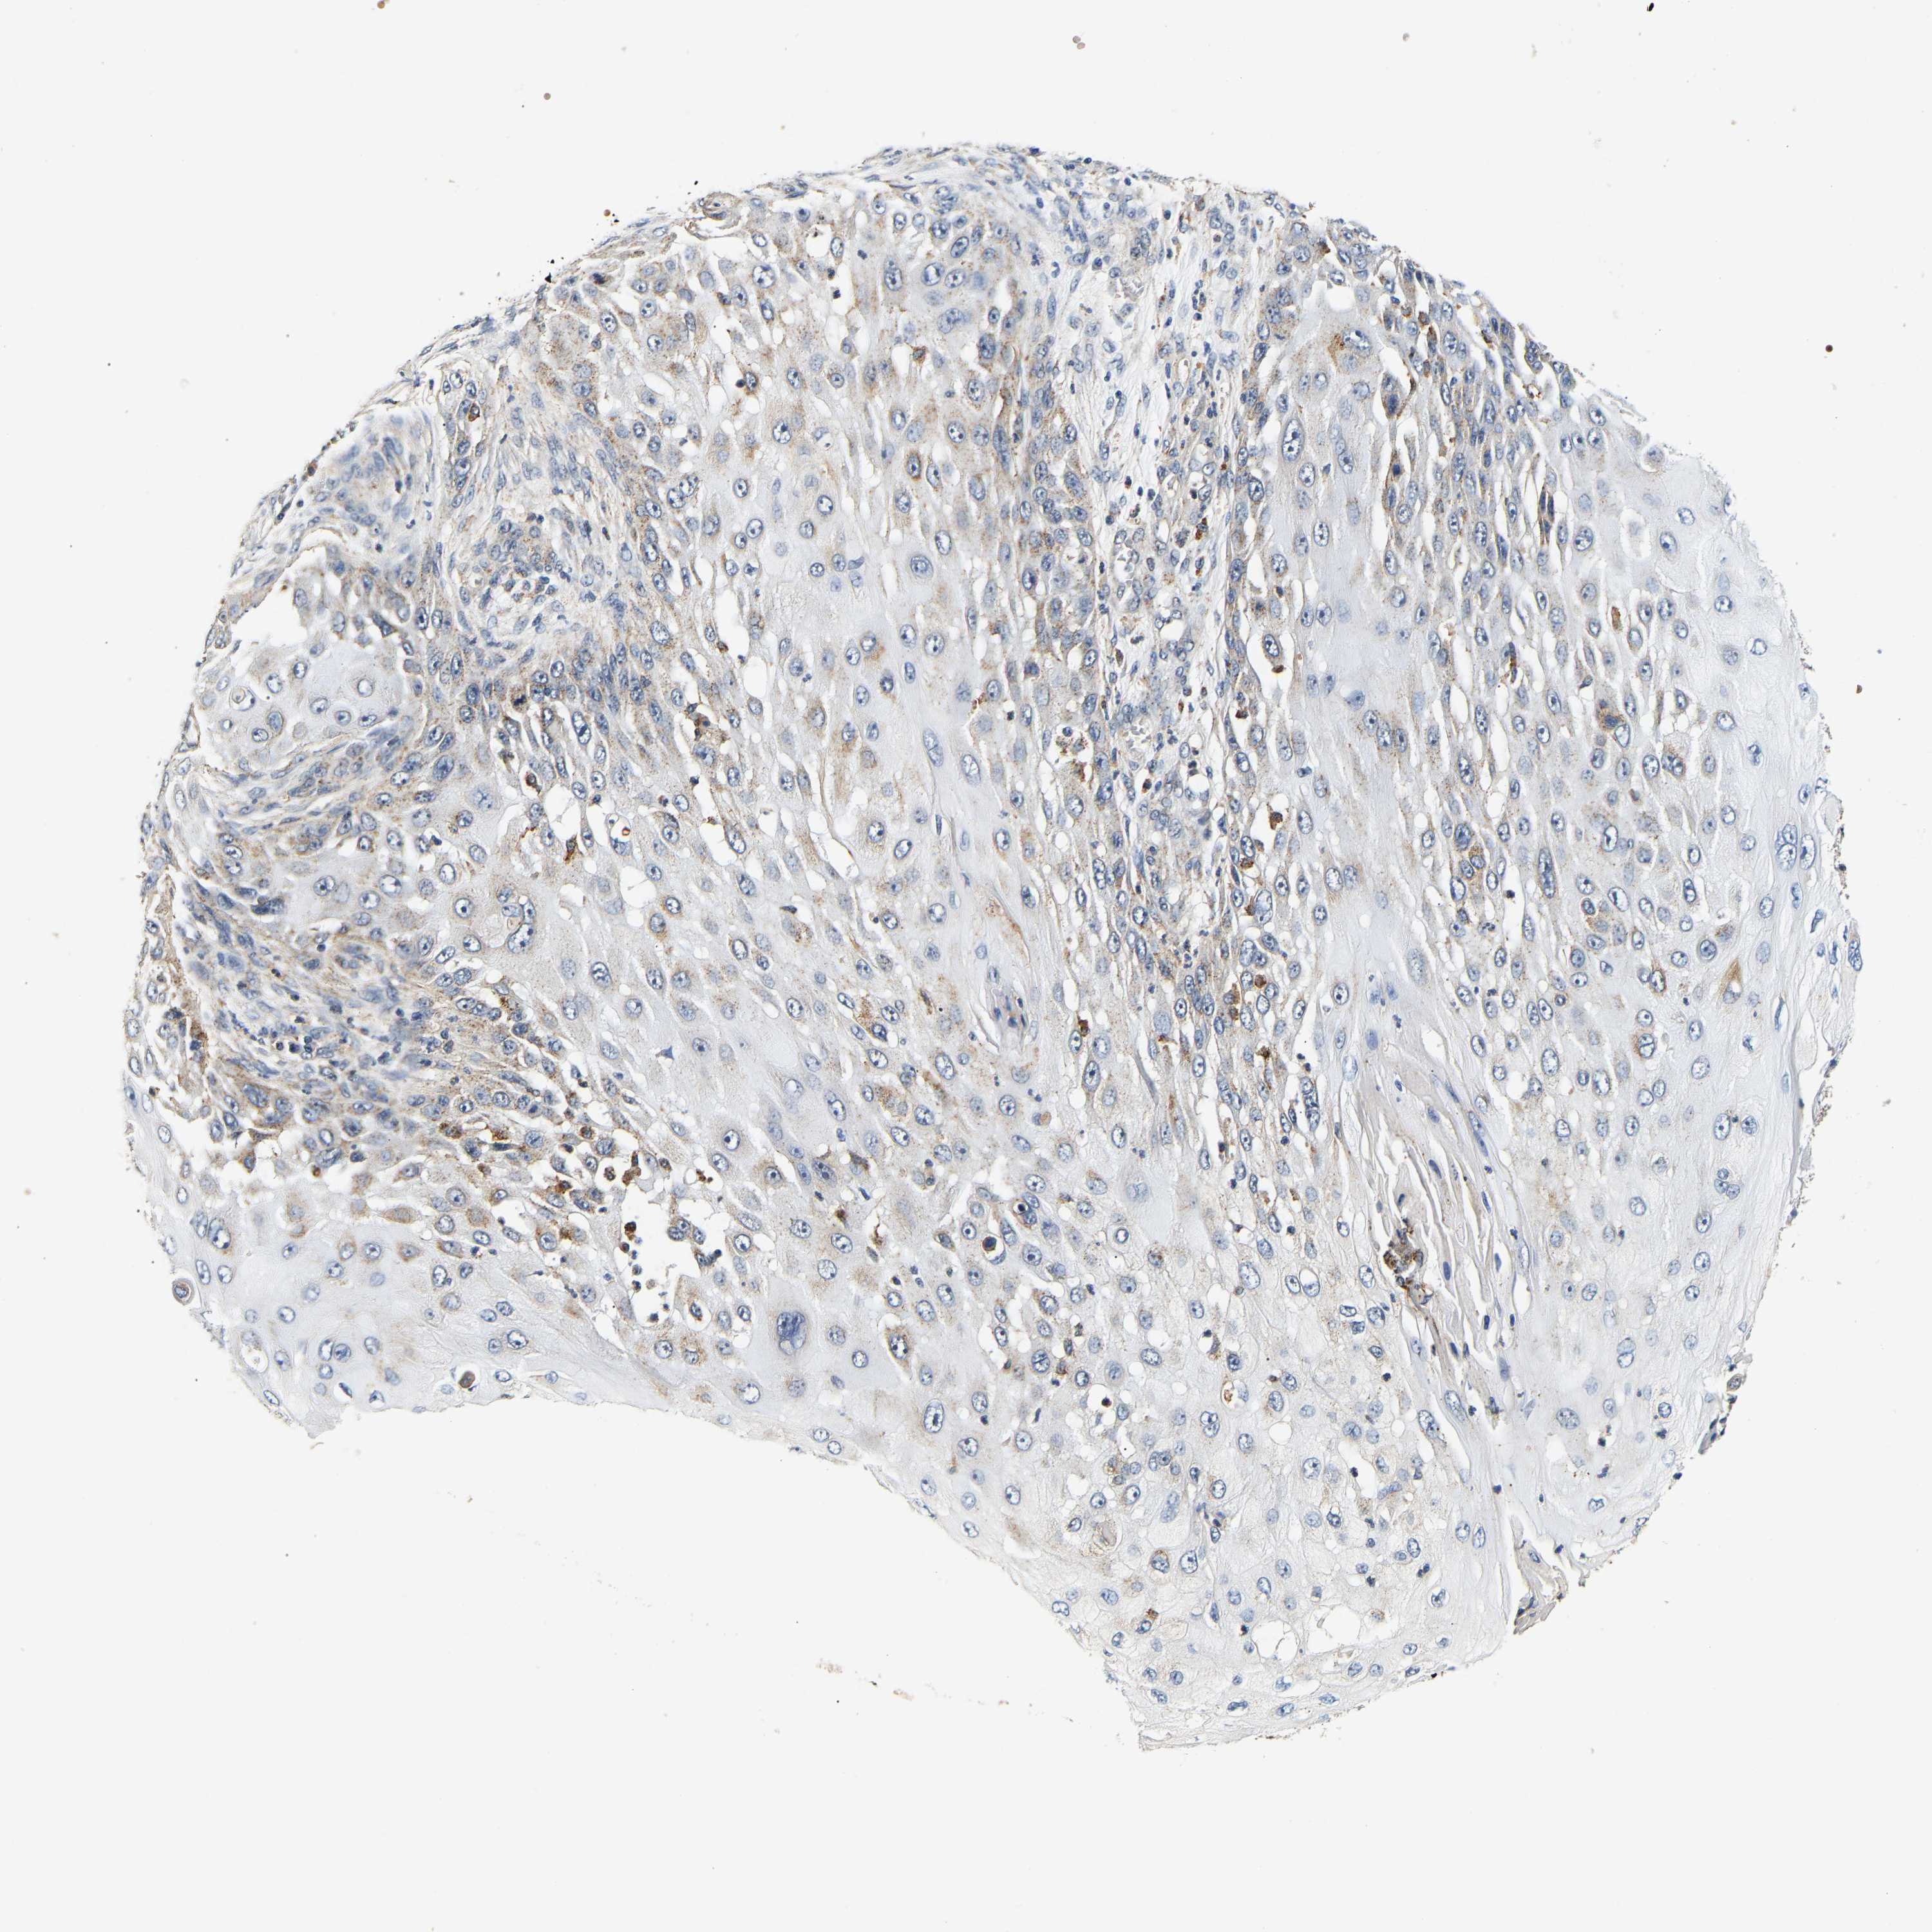

CANCER SKIN CANCER Show tissue menu

SKIN CANCER - Protein expressioni

A mouse-over function shows sample information and annotation data. Click on an image to view it in a full screen mode. Samples can be filtered based on level of antibody staining by selecting one or several of the following categories: high, medium, low and not detected. The assay and annotation is described here.

Each image is clickable and will lead to virtual microscopy that enables deeper exploration of all samples and also displays staining intensity scores, fraction scores and subcellular localization as well as patient and tissue information for each sample.

Antibody HPA019708

Staining

High

Medium

Low

Not detected

Intensity

Strong

Moderate

Weak

Negative

Quantity

>75%

75%-25%

<25%

None

Location

Nuclear

Cytoplasmic/membranous

Cytoplasmic/membranous,nuclear

Basal cell carcinoma

Squamous cell carcinoma, NOS

Squamous cell carcinoma, metastatic, NOS